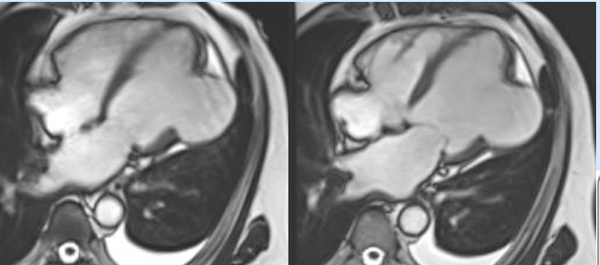

LV aneurysm